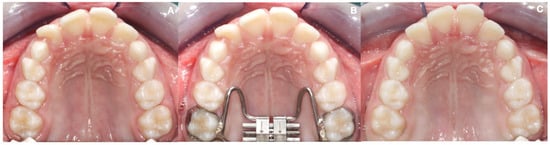

2.1. Treatment Protocol